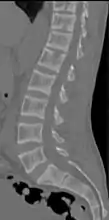

Subchondral resorption in the sacroiliac joint.[18] X-ray of a subtle "rugger jersey spine" due to sclerotic bands adjacent to the vertebral endplates.[18]

X-ray of a subtle "rugger jersey spine" due to sclerotic bands adjacent to the vertebral endplates.[18] CT scan of the same case.[18]

CT scan of the same case.[18]